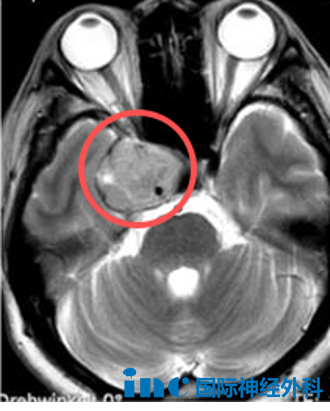

曾一度或当今仍被许多人视为“无人之地”的海绵窦区因其复杂的结构和密集的神经、血管,至今令人畏惧。

北京时间2025年10月22日,巴教授于苏州大学附属第四医院完成这台海绵窦区占位病变示范手术。

手术难在何处?在于其位置深、解剖关系错综复杂。该区域不仅包绕颈内动脉,更密集走行着动眼神经、滑车神经、三叉神经和外展神经等重要颅神经。术中稍有不慎,极可能导致功能障碍。因此,手术的核心目标是在全力保护血管与神经功能的基础上,最大限度地切除病变。

最终,在巴教授与国内神经外科团队的紧密协作下,这个血供丰富的肿瘤得到了满意的切除。